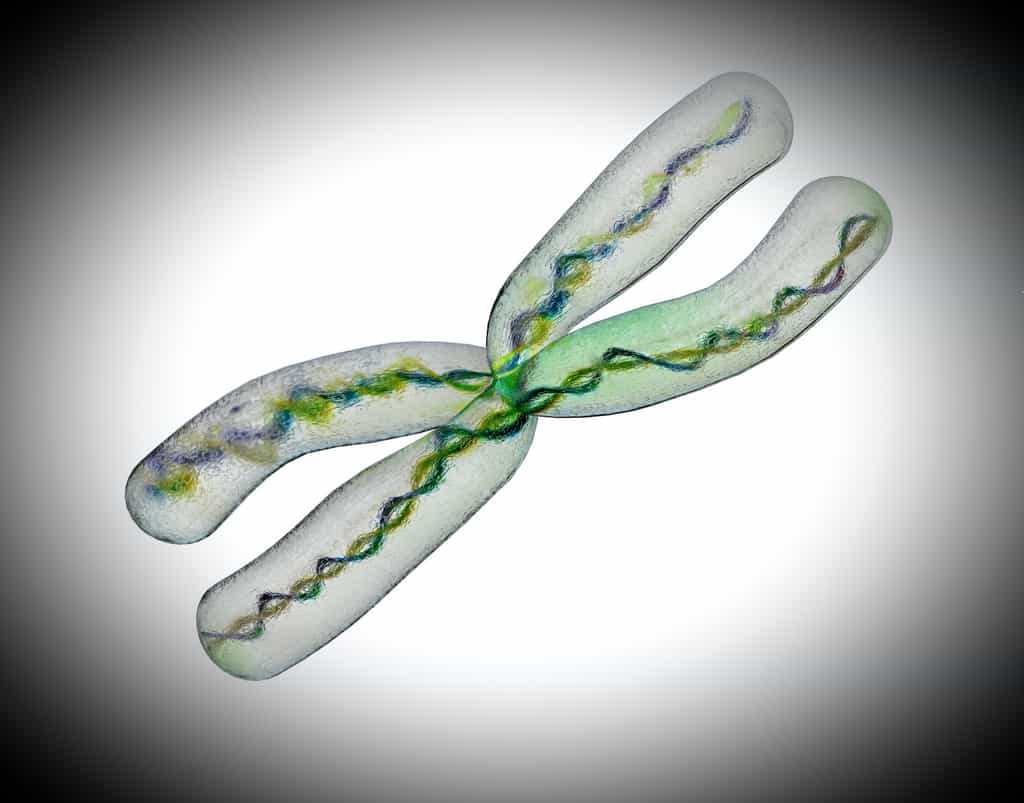

En 2003, le séquençage complet du génome humain a été annoncé. Si cette cartographie couvre 99 % des trois milliards de bases ADN du génome, il reste de nombreux trous et séquences manquantes sur les différents chromosomes. Car le génome n'a pas été séquencé en une seule fois : c'est une sorte de gigantesque puzzle reconstruit à partir de séquences d'ADN mises bout à bout, ce qui entraîne des discontinuités et des répétitions. Certaines zones contiennent ainsi de nombreuses séquences redondantes, ce qui rend particulièrement difficile la reconstruction. Imaginez un puzzle avec un grand ciel bleu où l'on n'aurait aucun indice sur la forme et l'emplacement des pièces qui le composent. Et plus les séquences sont petites, plus le casse-tête est compliqué. Ces répétitions sont particulièrement abondantes dans la zone centrale du chromosome, là où les télomères se croisent, car l'ADN y est très enchevêtré.

Il restait cependant de multiples ruptures dans le génome que les chercheurs ont dû corriger manuellement. Ils se sont notamment appuyés sur les variantes dans les séquences répétitives pour servir de marqueurs, utilisés ensuite pour aligner et relier les séquences entre elles. « Nous avons utilisé un processus itératif sur trois plateformes différentes pour ajuster le séquençageséquençage et atteindre un haut niveau de précision », indique Karen Miga. Au total, l'équipe a réussi à compléter les 29 trous présents sur le chromosome X dans la base de donnéesbase de données du génome de référence.

Après le chromosome X, l'équipe s'est attelée au séquençage des autres chromosomes. Mais cela risque de s'avérer un peu plus compliqué, notamment concernant les chromosomes acrocentriques (13, 14, 15, 21 et 22), qui ont un centromèrecentromère très grand et donc beaucoup plus de répétitions.